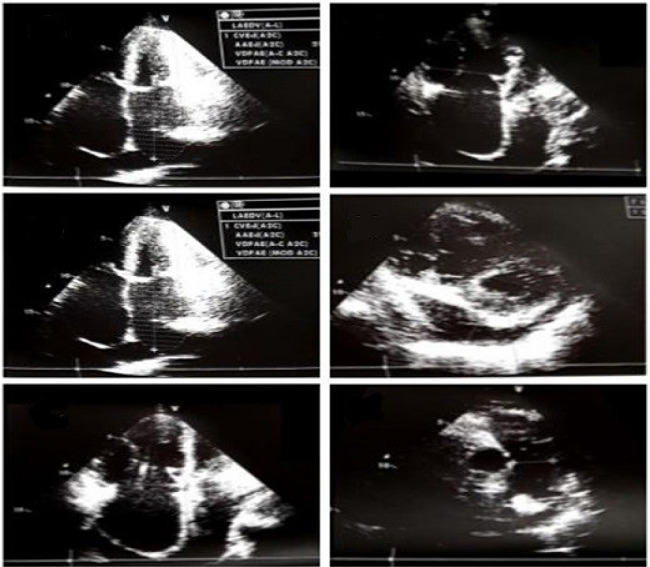

The patient also had a transthoracic echocardiogram showing an opening in the dome of the mitral valve with significant mitral stenosis, biatrial and right ventricular enlargements, moderate/significant tricuspid insufficiency, mild pulmonary arterial hypertension, and pericardial effusion with no hemodynamic repercussions (Figure 2).